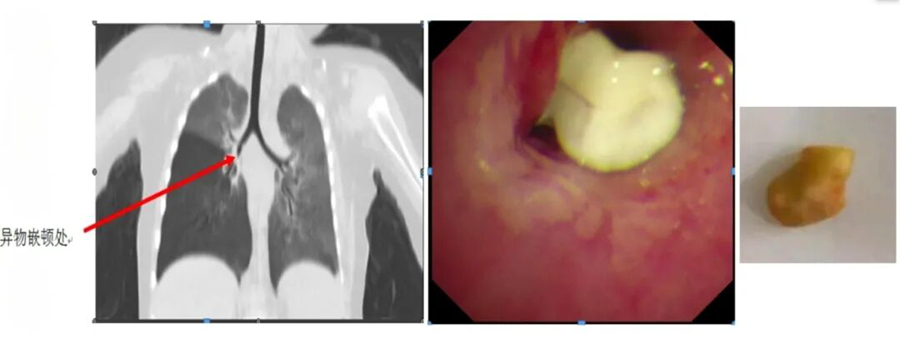

有一名患兒反復(fù)“肺炎”半年多,在當(dāng)?shù)蒯t(yī)院多次治療仍不見好轉(zhuǎn),家長慕名找到王文棣。她仔細(xì)為患兒聽診,敏銳地捕捉到孩子雙肺呼吸音左右不對稱這一關(guān)鍵線索,通過電子纖維支氣管鏡檢查揪出了“真兇”,竟是半粒花生米堵在了患兒的右主支氣管管口。當(dāng)異物被成功取出后,孩子的 “肺炎”再也沒有復(fù)發(fā)。